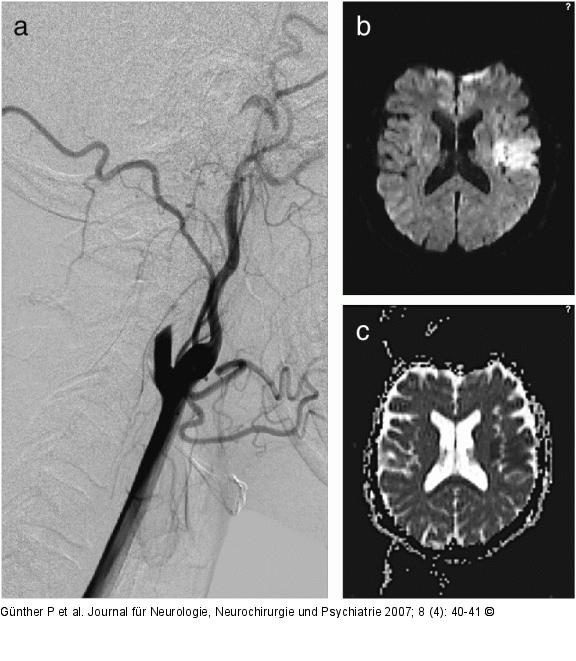

Abbildung 1: Arteria carotis - Dissektion Diffusionsgewichtete MR- sowie repräsentative Angiographieaufnahme einer 37jährigen Patientin mit Dissektion der linken A. carotis interna (ACI) unter jahrelanger Therapie mit D-Penizillamin bei Morbus Wilson. Die Angiographie (a) zeigt einen spitz auslaufenden Verschluß des proximalen Gefäßabschnittes und die MRT (b, c) einen Mediaterritorialinfarkt mit entsprechender Diffusionsstörung (DWI, B1000[trace] [b] und ADC-Map [c]). |

Diffusionsgewichtete MR- sowie repräsentative Angiographieaufnahme einer 37jährigen Patientin mit Dissektion der linken A. carotis interna (ACI) unter jahrelanger Therapie mit D-Penizillamin bei Morbus Wilson. Die Angiographie (a) zeigt einen spitz auslaufenden Verschluß des proximalen Gefäßabschnittes und die MRT (b, c) einen Mediaterritorialinfarkt mit entsprechender Diffusionsstörung (DWI, B1000[trace] [b] und ADC-Map [c]). |